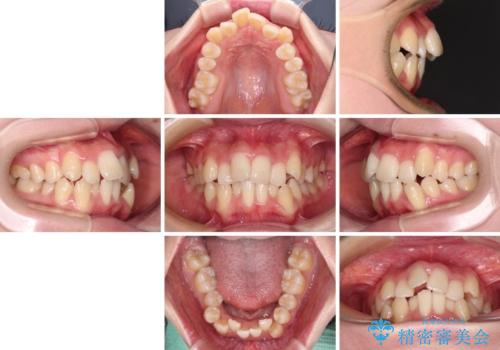

- 上下前歯の八重歯やデコボコと、唇の閉じにくさを気にして来院された患者様です。

口元の突出感を改善するため、上下左右の第一小臼歯4本を抜歯し、ワイヤー装置にて矯正治療を行うこととしました。

デコボコの解消で歯が磨きやすくなり、抜歯矯正により口元の突出感が大幅に改善され、スッキリした口元になりました。